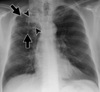

Diagnóstico de atelectasia

Sinais e sintomas e TC